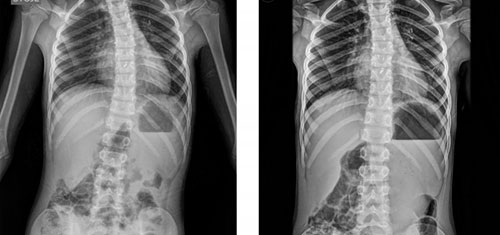

Искривлением позвоночного столба в боковой плоскости является сколиоз. Наблюдается болезнь у каждого второго человека. Чаще всего он начинает развиваться у детей школьного возраста. Сколиоз у взрослых образуется в результате малоподвижного образа жизни и сидячей работы. В результате одно плечо становится выше другого, а лопаточные углы располагаются на разных уровнях.

Сколиоз — это искривление позвоночника, которое требует внимательного подхода к диагностике и лечению. Врачи-ортопеды играют ключевую роль в этом процессе, так как именно они специализируются на заболеваниях опорно-двигательного аппарата. При первом обращении пациенту может быть назначено рентгенографическое исследование для определения степени искривления. В зависимости от результатов, ортопед может рекомендовать различные методы лечения, включая физиотерапию, ношение корсета или, в более сложных случаях, хирургическое вмешательство. Также важно учитывать мнение неврологов, которые могут оценить влияние сколиоза на нервную систему и предложить дополнительные методы реабилитации. Таким образом, комплексный подход с участием различных специалистов обеспечивает наиболее эффективное лечение этого заболевания.

Решение при искривлении позвоночника, то есть, к какому врачу обратиться, будет приниматься только после рентгеновского обследования. Если степень заболевания начальная, то лечить может терапевт. Если потребуется, то дополнительно назначается консультация у ортопеда и невропатолога.

Ортопед исправляет сильных деформаций в системе костей и суставов. А также избавляется от искривления легкой степени на ранних стадиях развития. Терапия в данном случае назначается только в соответствии с результатами анализов и после прохождения рентгеновского обследования. Но ортопед не всегда может излечить больного самостоятельно, в некоторых случаях он дополнительно привлекает других специалистов и создается комплексный метод терапии.